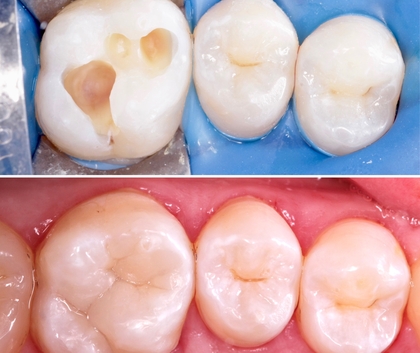

До

После

В стоматологическом центре "5 Принципов" в Симферополе лечение кариеса — это не просто процедура, а путь к здоровью зубов и уверенной улыбке. Мы предлагаем современные методики, индивидуальный подход и комфорт на каждом этапе. Наши специалисты используют безболезненные технологии, минимальные сроки и эстетичные материалы, чтобы восстановить поверхность зуба максимально естественно. Примеры работ: безопасная диагностика с помощью цифровой панорамной съемки, точная локализация очага кариеса, удаление пораженной ткани и пломбирование композитными материалами под оттенок зуба. Важно не только вылечить, но и предотвратить повторное развитие кариеса: наши рекомендационные планы включают фторирование, реминерализацию эмали и советы по гигиене. Мы уделяем внимание функциональности зубов и их долговечности: после лечения вы сможете наслаждаться твердостью зубов, нормальной прикусной нагрузкой и естественным цветовым соответствием улыбки. В "5 Принципах" комфорт пациентов — приоритет: современные анестезия и технологии снижают дискомфорт до минимума, а дружелюбная атмосфера помогает забыть о тревоге перед посещением. Мы гордимся результатами: здоровые зубы, красивая улыбка и уверенность наших пациентов в Симферополе. Запишитесь на консультацию — и убедитесь, как эффективно может работать лечение кариеса в нашем центре.